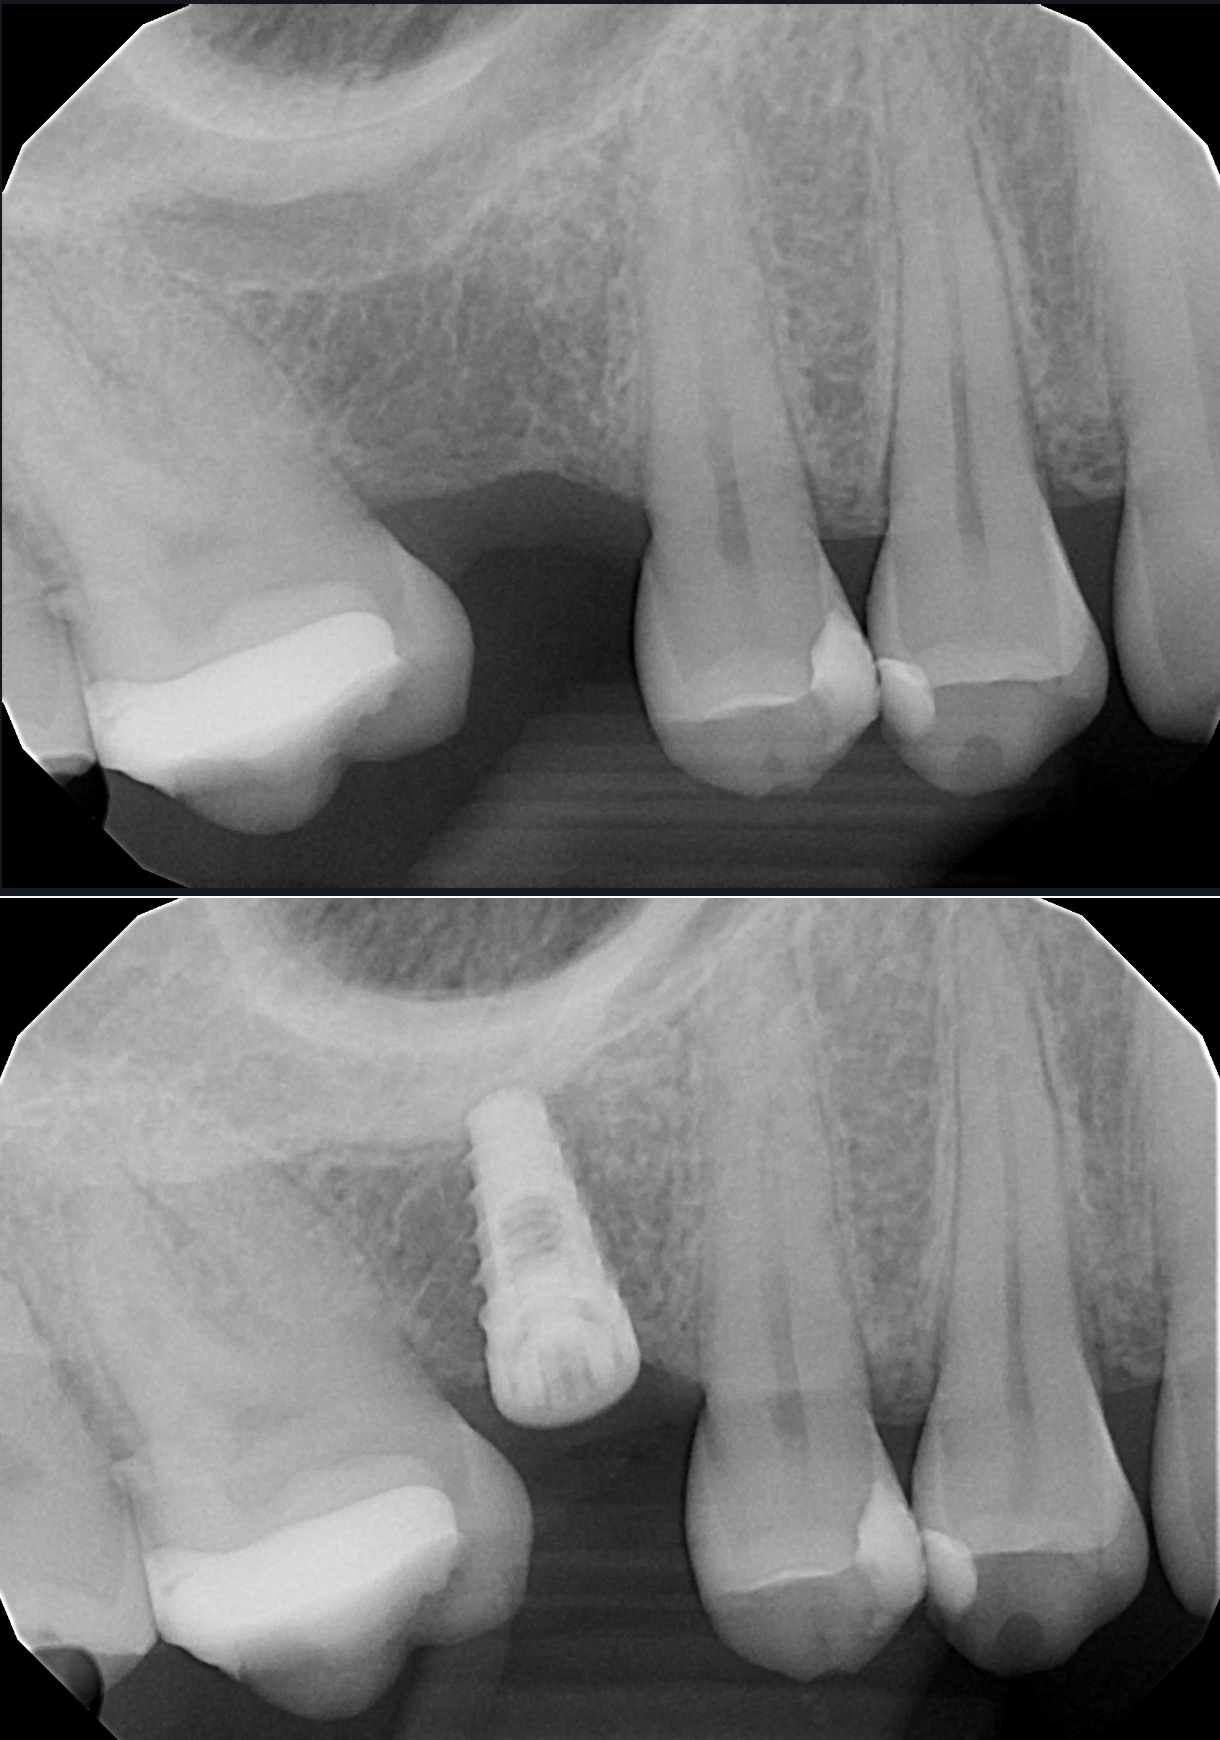

A selection of before and after X-ray images from cases I have performed, showcasing single implants placed in posterior gaps and single-tooth spaces. This is often the ideal solution in these situations.